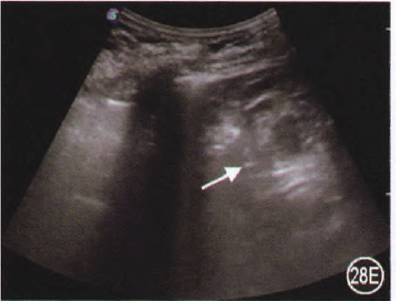

进行肺部超声检查时,首先要确定胸膜的位置,将探头置于两个肋骨之间时,会看到屏幕外围两侧有宽约2 cm的高回声曲线,胸膜线位于屏幕中央,两侧肋骨下方,在脏层胸膜和壁层胸膜交界处形成的第一条高回声曲线,其形态类似蝙蝠,故称为“蝙蝠征”。之后再去观察有无“肺滑动征”,即脏层胸膜和壁层胸膜随呼吸而相互滑动或闪动,肺滑动征提升我们两层胸膜之间无气无水,胸膜无黏连或融合。此外,在超声上还能看到A线,即在胸膜线下与胸膜线平行、相互之间等距的高回声曲线。正常肺充气状态即为A线+肺滑动征。

图片